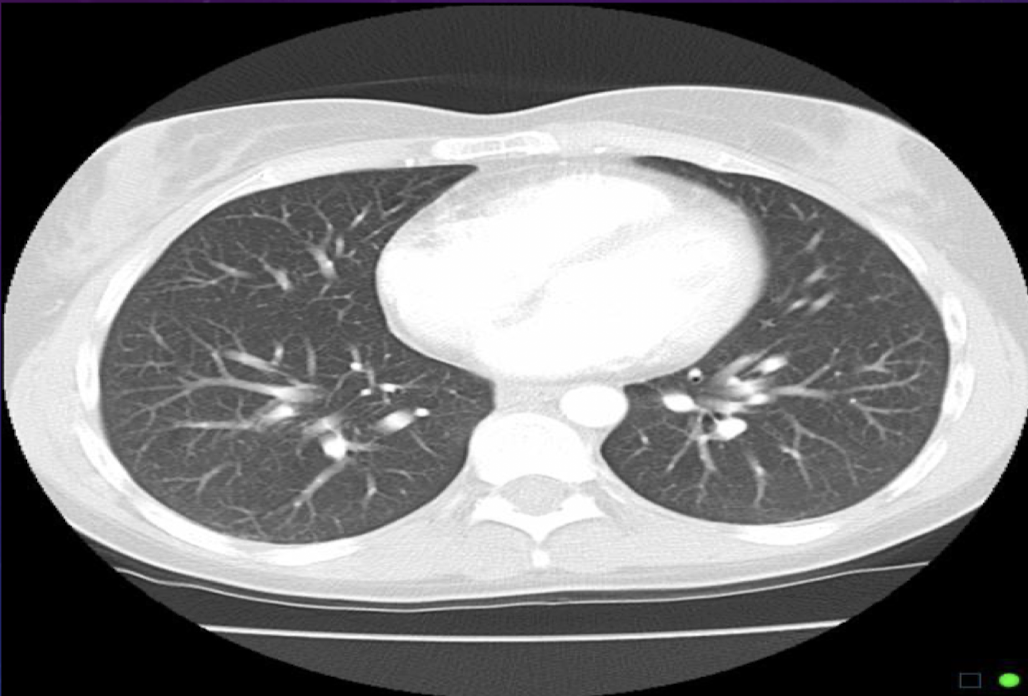

What are the different WW, WL needed for when visualizing a CT scan of the thorax?

1. Mediastinum

2. Air filled lungs

3. Ribs and calcifications

<p>For a lung window for a thorax scan, why do we want a wide WW?</p>

For a lung window for a thorax scan, why do we want a wide WW?

To show more gray for smaller structures

<p>To show more gray for smaller structures</p>